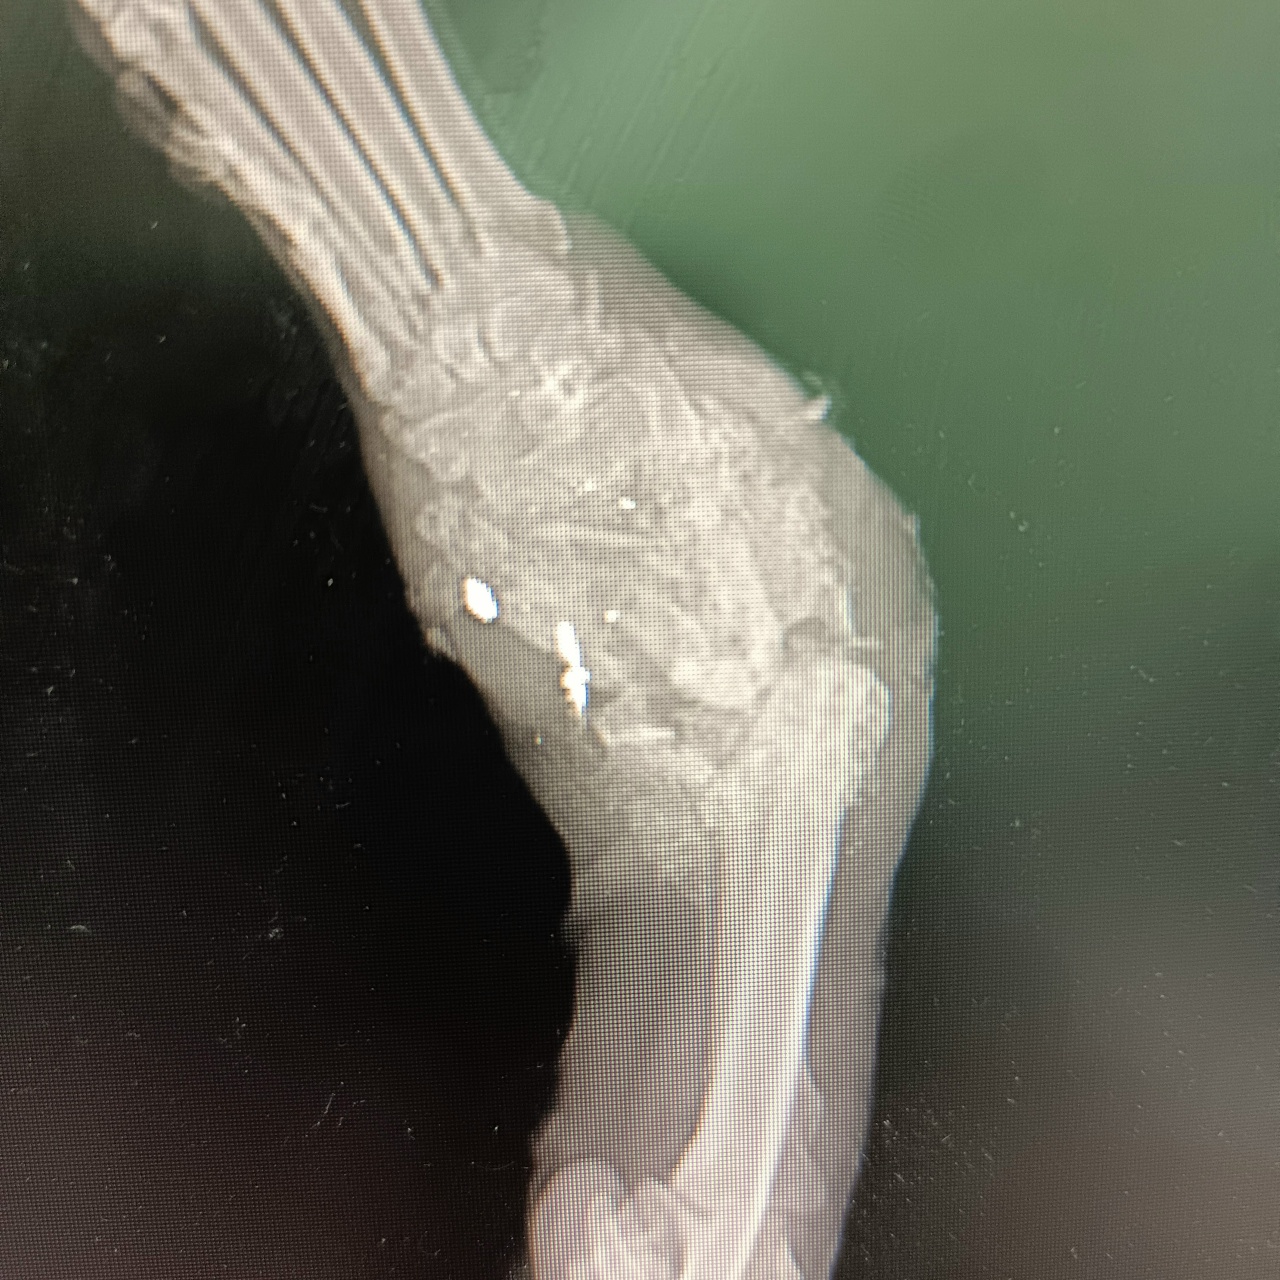

Пёс со множеством пуль в грудной клетке и лапе

По первым фотографиям с места была масса предположений: драка, капкан и даже поезд, но обследование в "Клинике ветеринарной медицины" показало совершенно другую причину.

Пули. Много пуль. В грудной клетке и в лапе.

Но самое печальное, что запястный сустав - разрушен тотально.